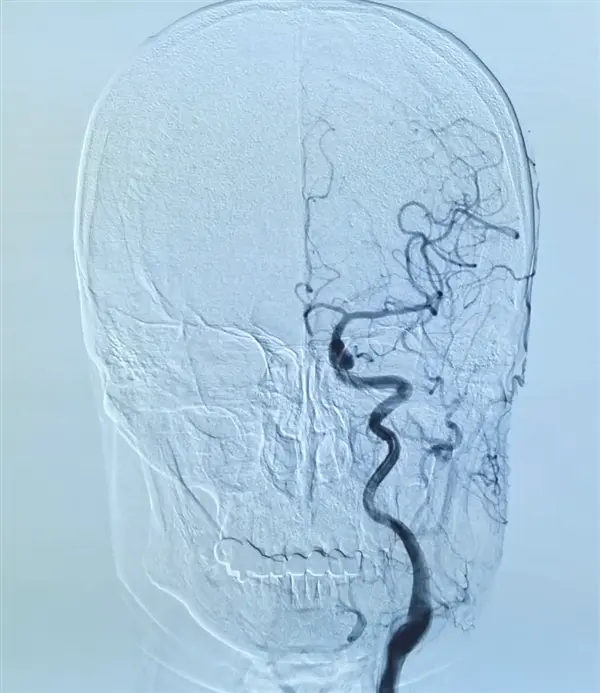

“幸运”的是,家人曾经得过脑卒中,所以立刻将其送医,及时通过动脉溶栓手术治疗,半小时后就完全恢复。